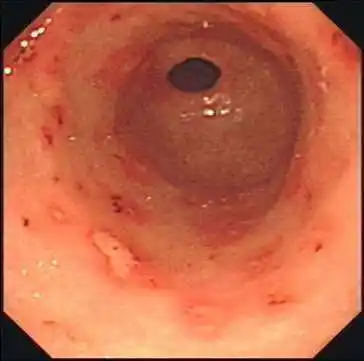

求助慢性胃炎糜烂出血反流性食道炎治疗方案

慢性非萎缩性胃炎伴出血,糜烂的图片 - 好大夫在线

解读胃镜报告——糜烂,溃疡和肠化_胃镜_胃镜相关疾病 - 好大夫在线

慢性胃炎